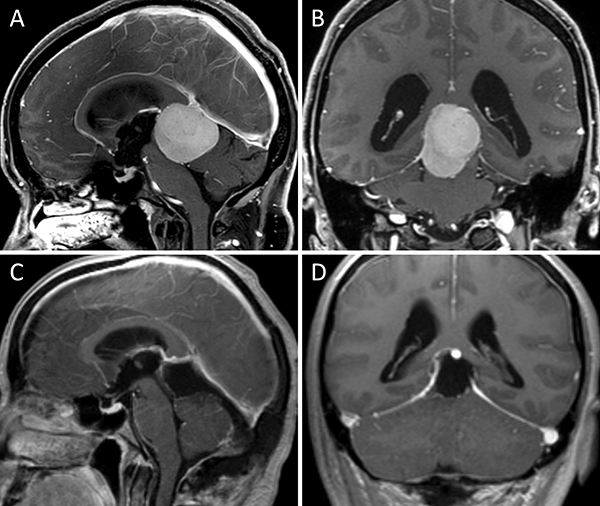

Figura 1. Meningioma tentorial medial. A-B: RM preoperatoria; C-D: RM postoperatoria.

Las figuras 1 a 11 muestran una serie de casos ilustrativos representativos de la presente clasificación (Figuras 1-11).

La figura 12 es un dibujo esquemático que sintetiza la presente clasificación (Figura 12).